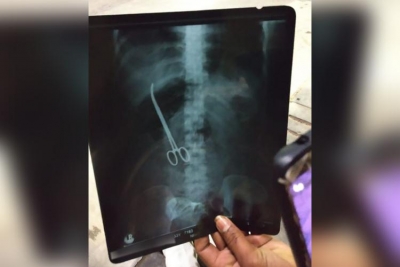

Đau bụng dữ dội, cô gái đi khám phát hiện chiếc kéo nằm trong bụng đã 3 tháng

Bệnh viện đã thực hiện một cuộc phẫu thuật miễn phí để lấy chiếc kéo ra khỏi bụng cô gái.